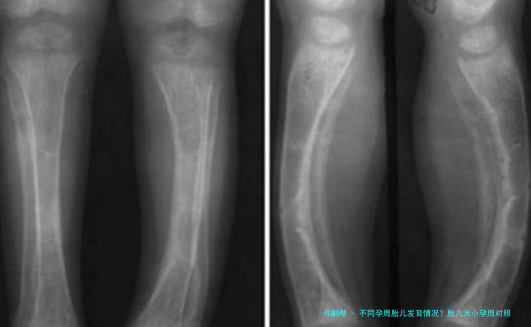

自然,每个宝宝的发育节奏不相同,有的快些许,某些慢些许,只要在正常范围内就不必太担心。医生也会通过B超来测量宝宝的双顶部直径、腹部周长、股骨长等指标,综合判断宝宝的成长情形。